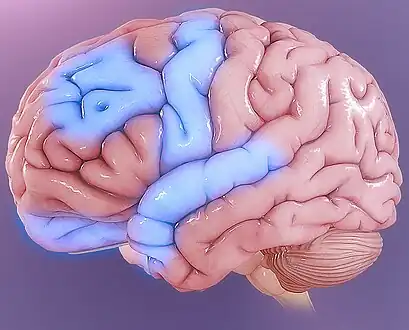

Functional neuroimaging during symptom provocation has observed abnormal activity in the orbitofrontal cortex, left dorsolateral prefrontal cortex, right premotor cortex, left superior temporal gyrus, globus pallidus externus, hippocampus and right uncus. Weaker foci of abnormal activity were found in the left caudate, posterior cingulate cortex and superior parietal lobule.[61] However, an older meta analysis of functional neuroimaging in OCD reported the only consistent functional neuroimaging findings have been increased activity in the orbital gyrus and head of the caudate nucleus, while ACC activation abnormalities were too inconsistent.[62] A meta analysis comparing affective and non affective tasks observed differences with controls in regions implicated in salience, habit, goal-directed behavior, self-referential thinking and cognitive control. For non affective tasks, hyperactivity was observed in the insula, ACC, and head of the caudate/putamen, while hypoactivity was observed in the medial prefrontal cortex (mPFC) and posterior caudate. Affective tasks were observed to relate to increased activation in the precuneus and posterior cingulate cortex(PCC), while decreased activation was found in the pallidum, ventral anterior thalamus and posterior caudate.[63] The involvement of the cortico-striato-thalamo-cortical loop in OCD as well as the high rates of comorbidity between OCD and ADHD have led some to draw a link in their mechanism. Observed similarities include dysfunction of the anterior cingulate cortex, and prefrontal cortex, as well as shared deficits in executive functions.[64] The involvement of the orbitofrontal cortex and dorsolateral prefrontal cortex in OCD is shared with bipolar disorder and may explain their high degree of comorbidity.[65] Decreased volumes of the dorsolateral prefrontal cortex related to executive function has also been observed in OCD.[66]

People with OCD evince increased grey matter volumes in bilateral lenticular nuclei, extending to the caudate nuclei, with decreased grey matter volumes in bilateral dorsal medial frontal/anterior cingulate gyri.[67][68] These findings contrast with those in people with other anxiety disorders, who evince decreased (rather than increased) grey matter volumes in bilateral lenticular / caudate nuclei, as well as decreased grey matter volumes in bilateral dorsal medial frontal/anterior cingulate gyri.[68] Increased white matter volume and decreased fractional anisotropy in anterior midline tracts has been observed in OCD, possibly indicating increased fiber crossings.[69]

Some parts of the brain showing abnormal activity in OCD

Some parts of the brain showing abnormal activity in OCD